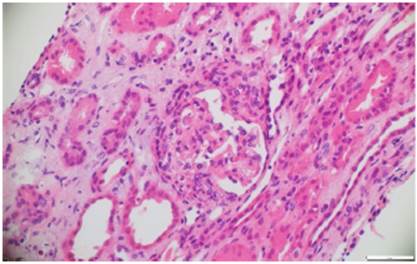

A pesar del manejo con pulsos de ciclofosfamida, la paciente presentó marcado deterioro clínico con requerimiento de diálisis peritoneal. Se realizó una segunda biopsia en nuestra institución, con evidencia de glomerulonefritis pauciinmune esclerosante con menos del 10% de semilunas fibrocelulares, fibrosis intersticial y atrofia tubular severa (figs. 1 y 2). Posteriormente, se tomaron niveles de MPO-ANCA y PR3-ANCA por inmunofluorescencia indirecta, los cuales fueron negativos.

Figura 1 Hematoxilina y eosina. Glomérulo que presenta glomeruloesclerosis focal y segmentaria. En el intersticio se observa edema e infiltrado inflamatorio mononuclear con atrofia tubular. 10x.

Figura 2 Hematoxilina y eosina. Glomérulo con proliferación extracapilar y formación de semilunas fibroepiteliales que obstruyen el penacho glomerular. 10x.